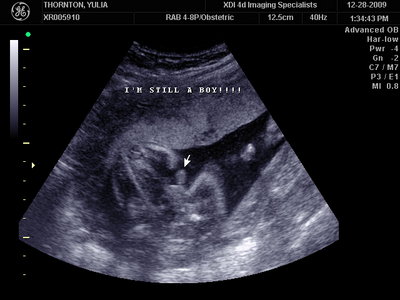

Ну ладно, тогда и я нашего писюна покажу  Надеюсь, Джеффри на меня не обидится Вот это в 23 недели: (там оборудование переключалось из режима 3Д в обычный 2Д)

| Вложения: |

MY BABY SONO!_2_15.JPG [ 112.35 КБ | Просмотров: 1114 ]

Sweetheart75 писал(а): Ну ладно, тогда и я нашего писюна покажу  Надеюсь, Джеффри на меня не обидится Вот это в 23 недели: (там оборудование переключалось из режима 3Д в обычный 2Д) Oоо, такое достоинство невозможно не заметить  А в 30 недель так вообще!